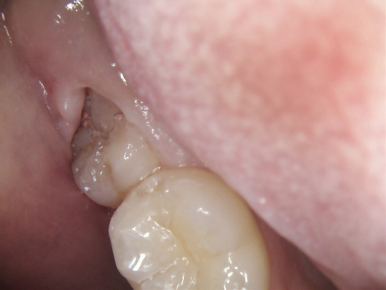

2.親知らずが虫歯になると、その手前の歯も虫歯になる可能性があります

一番右奥の親知らずは良く磨けず、虫歯になることが多いのです。早く抜いて、前の歯が虫歯にならないようにしなければなりません。